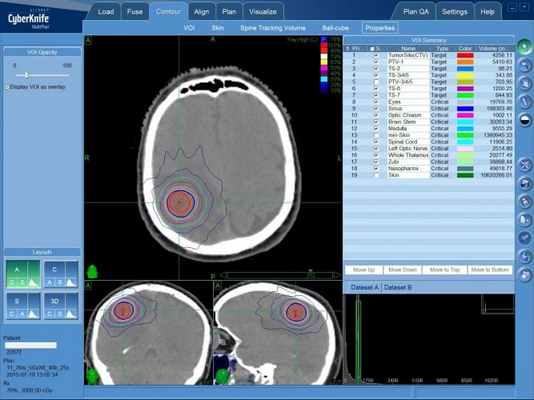

Решение о лечении ганглионевромы (ганглиоцитомы), обнаруженной случайно, без клинических проявлений необходимо принимать крайне взвешенно, оценивая возможные риски. В случае, если наблюдается динамика роста или нарастание симптомов без увеличения опухоли в размерах, пациентам показано радикальное лечение, в качестве которого могут применяться как традиционное нейрохирургическое вмешательство, так и радиохирургия на КиберНоже (предпочтительнее), при которой риск повреждения здоровых тканей практически отсутствует (КибнрНож воздействует дистанционно, без разрезов).

Радиохирургическая система КиберНож

Преимущество КиберНожа состоит в неинвазивности лечения ганглиоцитомы — операция в общепринятом понимании не проводится: нет повреждения ни кожных покровов, ни нарушения целостности мозговых оболочек. Высокая доза ионизирующего излучения, которая приводит к разрушению тканей опухоли либо остановке ее роста, подается точно в область расположения опухоли, оставляя нетронутыми (в пределах безопасных, легко переносимых, доз) здоровые ткани, через которых тонкие пучки излучения проходят на пути в опухоль.

Ганглиоцитома (ганглионеврома) — план лечения на КиберНоже. Красным контуром отмечено пространство, подлежащее облучение разовой высокой дозой ионизирующего излучение, которое остановит биологическую активность опухолевых клеток.